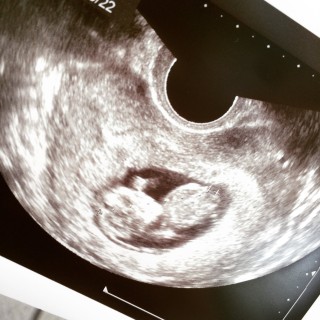

毎日毎日不安でしたが先生に順調って言われて凄く安心しました! 前回のエコーよりも大きくなっていてだんだん実感もわいてきました、、これからも順調に育ちますように☆

赤ちゃんらしいポーズをしてました。4センチにまで成長しました。心音も聞かせてもらえて泣きそうになりました。